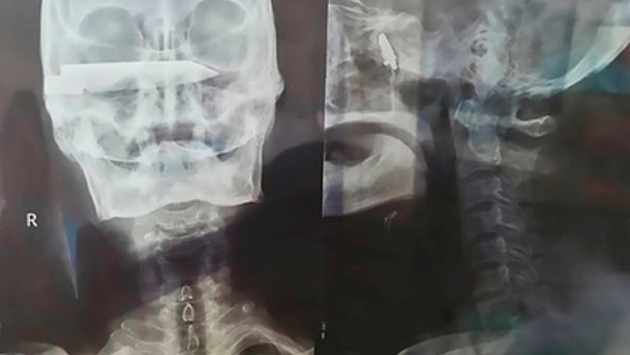

Мужчина прожил 26 лет с десятисантиметровым ножом в голове

В Китае врачи прооперировали мужчину, проходившего 26 лет с ножом в голове. Об этом сообщает газета The Daily Star.

© SFMU 1st Hospital

76-летний фермер рассказал, что преступники вонзили в него десятисантиметровый нож во время ограбления. Лезвие находилось слишком близко к жизненно важным органам, извлечь его мог только хирург с очень высокой квалификацией. В родном городе китайца никто из врачей не брался за проведение сложной операции. В результате мужчина 26 лет прожил с ножом в голове, спасаясь лишь обезболивающими.